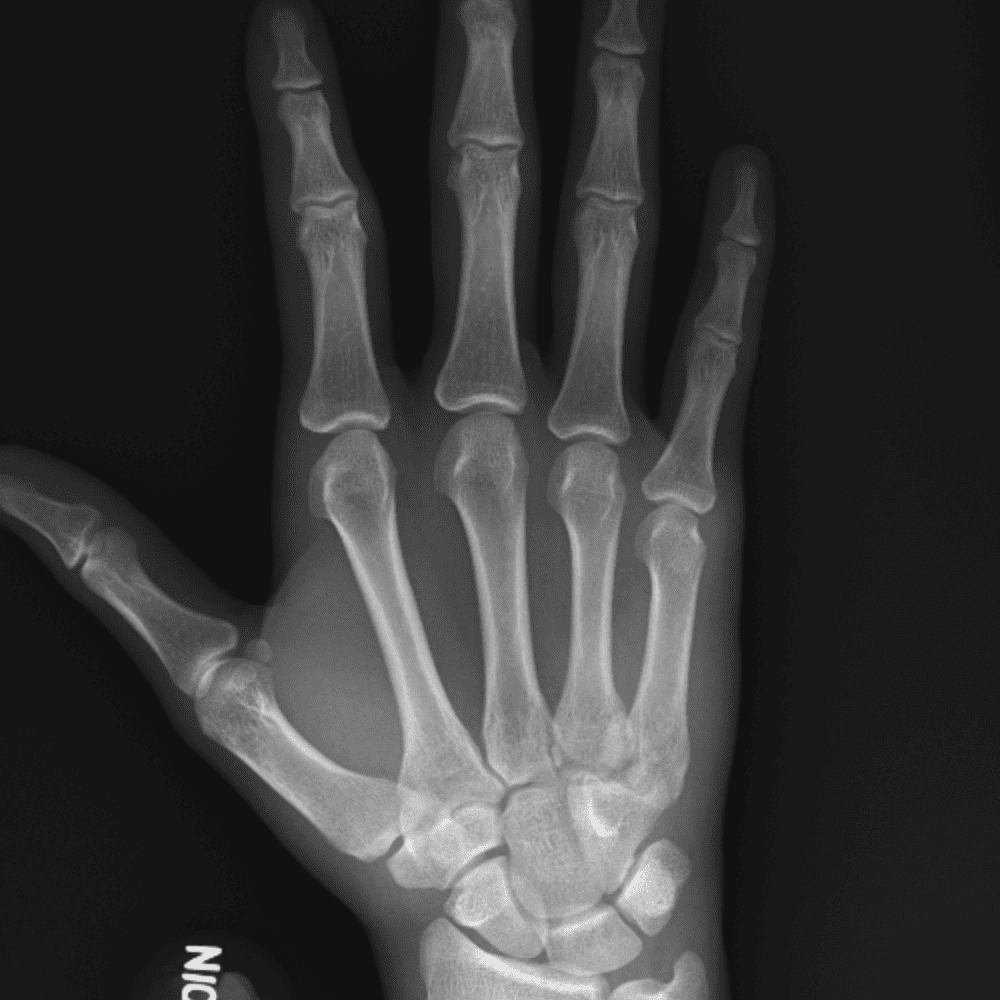

Simuliert den Dienst durch subtile oder schwierige Fälle und einige Normalbefunde.

30 Fälle